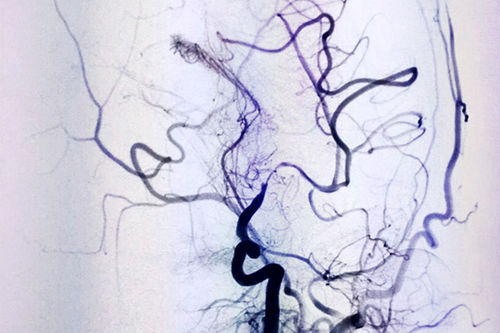

DSA血管介入診斷和治療,像一種“血管藝術(shù)”,初看如水墨丹青一樣的術(shù)中影像圖,如同醫(yī)護(hù)人員用智慧和技巧繪制的生命圖譜。上海藍(lán)十字腦科醫(yī)院DSA血管介入診療是醫(yī)院特色科室,擁有非常完善和先進(jìn)的設(shè)備,李振并主任已經(jīng)使用DSA成功診斷和治療了很多大面積腦;颊。

DSA血管造影,仿佛醫(yī)生繪出的生命圖騰

術(shù)前DSA影像顯示,患者大腦中動脈血管70%以上狹窄